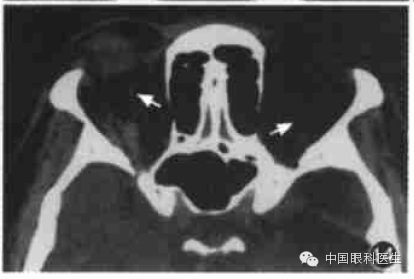

甲状腺相关眼病也称Graves'病,这是最常见的单侧和双侧眼球突出原因。临床上有眼睑退缩、上睑迟落等一些典型体征。而CT在疾病的不同时期显示出不同的形态学的改变,主要CT征包括:眼球突出、眼外肌肥厚、脂肪垫扩大,其中以眼外肌肥厚最常见(图12)。其受累频率依次是下直肌、内直肌、上直肌和外直肌,晚期提上睑肌、上斜肌均肥厚。甲状腺相关眼病的眼外肌肥厚特征为以肌腹梭形肥厚为主,边界清楚。但当下直肌肥厚做水平CT扫描时,易误诊为眶内肿瘤,此时应做冠状CT鉴别。

图12甲状腺相关眼病CT显示双侧内外直肌肌腹和眶尖部增厚,视神经受压,筛骨纸板向内移位(箭头)